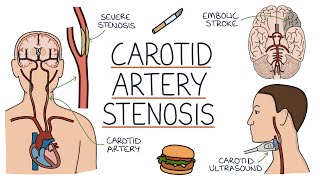

Common carotid Artery Anatomy - Origin , Course , Relations , Branches , Clinical anatomy - USMLE Understanding Carotid Artery Stenosis

Understanding Carotid Artery Stenosis

Common carotid Artery Anatomy - Origin , Course , Relations , Branches , Clinical anatomy - USMLE Understanding Carotid Artery Stenosis

Understanding Carotid Artery Stenosis